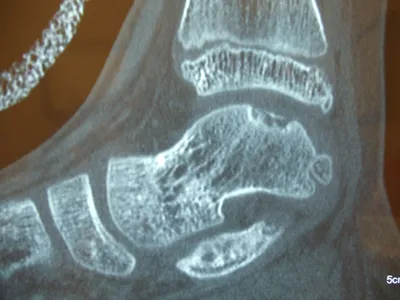

Intraop series of pics of a large osteochondral fracture on the shoulder of the talus in a teenage soccer player.

CT and MRI OCD Talus